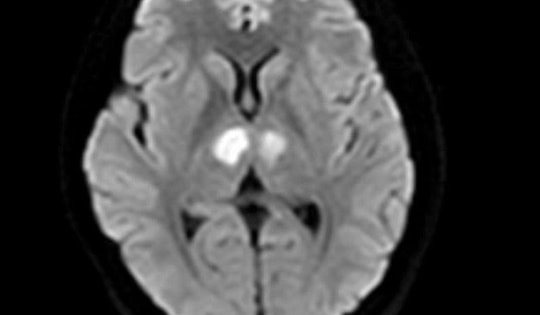

Người phụ nữ 21 tuổi ở Hà Nội bị tổn thương não nặng, thừa nhận sai lầm uống thuốc giảm cân mua trên mạng xã hội

Người phụ nữ 21 tuổi rơi vào tình trạng bất tỉnh, tổn thương não nặng do uống thuốc, thực phẩm chức năng giảm cân không rõ nguồn gốc.

Cô gái 26 tuổi tổn thương não sau 10 ngày uống thuốc giảm cân mua trên mạng

Người phụ nữ 26 tuổi đột ngột mất thị lực, tổn thương não sau 10 ngày uống thuốc giảm cân. Các bác sĩ chẩn đoán bệnh nhân ngộ độc chất cấm Sibutramine có trong sản phẩm chị mua trên mạng.